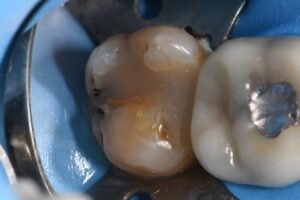

March 10, 2026 (Afternoon tea pics 2341.3: Kerr Simplishade | Rhondium DME | Garrison Dental Solutions – North America) Getting d o w n with DME. #RhondiumDME #KerrSimplishade #GarrisonCompositight Previous Post